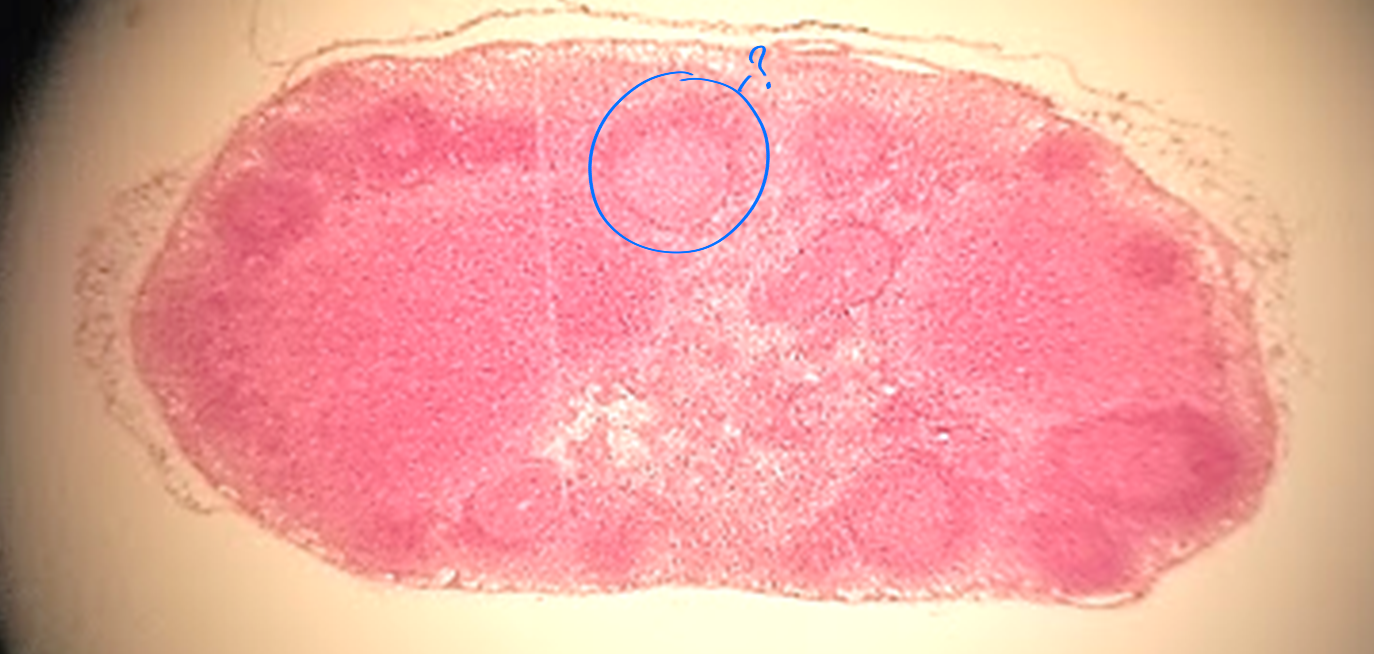

red pulp of spleen

what is outlined?

white pulp of spleen

medulla of lymph node

cortex of lymph node

follicle no germinal center

follicle germinal center